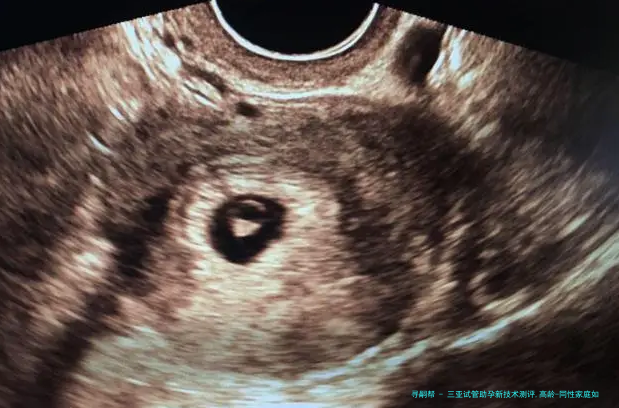

胚胎植入前基因学检查(PGD/PGS)已成为三亚主要潮流机构的标配,新一代测序技术将染色体异样检出率提升至99%以上,大幅减少高龄夫妻因卵子老化导致的早产风险。更前端的试探集结在CRISPR基因编辑,可修复地中海贫血、脊髓性肌肉萎缩症等单基因突变,虽暂处临床研究阶段,但为遗传性疾病家庭提供了新可能。

玻璃化冷冻技术使胚胎复苏存活率达百分之九十八,卵子保存复苏率进展百分之九十一。针对卵巢功能衰落者,线粒体体替换技术通过替换衰老细胞器,使42岁以上女性活产率从百分之十五跃升至28.7%。

三十八岁以上女性卵子非整倍体率超60%,需首先选择备有PGT-A(非整倍体筛查) 技术的机构,结合AI预测模型筛查染色体正常胚胎,将四十二岁临床妊娠率从12%提至39%。反复移植失败者,可以借助无创胚胎基因诊断(niPGT) 通过培育液游离DNA筛查,防止活检伤害胚胎,活产率提升至75%。